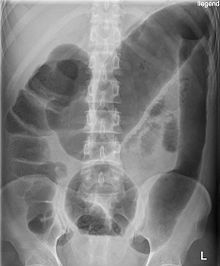

what is this condition

TOXIC MEGACOLON (acute deterioration of UC):